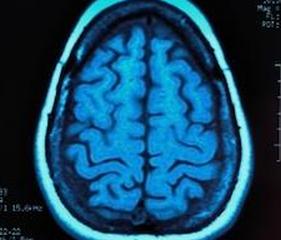

МРТ (магнитно-резонансная томография) — это медицинский тест, который похож на рентген, но МРТ использует радиочастотные импульсы и магнитное поле для получения изображений, а не излучения. Изображения появляются на мониторе компьютера, и их можно распечатать, передать в электронном виде или записать на компакт-диск.

Процедура визуализации использовалась для выявления повреждений головного мозга и опухолей, а также является обычным инструментом во многих исследованиях аутизма. Визуализирующий тест может быть наиболее многообещающим методом раннего выявления аутизма.

Правое и левое полушария мозга должны работать вместе, чтобы мозг функционировал должным образом. МРТ головного мозга может выявить аутизм, показывая дисфункцию связи. Исследователи из Университета Юты обнаружили, что МРТ может выявить проблемы в связи между полушариями мозга.

Николас Ланге — ведущий автор захватывающего исследования из больницы Маклин , филиала Гарвардского университета, в котором с 94-процентной точностью удалось обнаружить аутизм с помощью МРТ. Сканирование исследует шесть областей мозга, которые включают эмоциональное, языковое и социальное функционирование. В процессе визуализации использовалась диффузионно-тензорная визуализация, которая дополнительно уточняет магнитно-резонансную томографию.